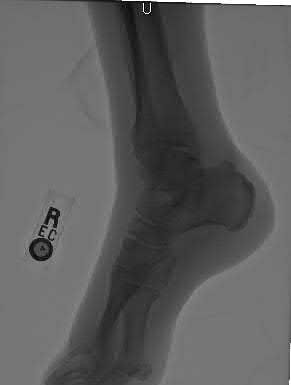

Figures A to C show radiographs of a 70 year-old male who fell on the ice 5 days ago. He could initially walk after the fall, but he is now unable to weight-bear on the leg due to pain. Physical examination shows diffuse ankle swelling, with no medial sided ankle tenderness. He is neurovascularly intact. The patient does not smoke and has no medical history. A gravity stress radiograph is demonstrated in Figure

D. After closed reduction, there is 2 mm of fracture displacement, no talar shift and the talocrural angle = 83 degrees. What is the most appropriate treatment?

Figure C demonstrates a lateral radiograph of a Weber B fibula fracture with a congruent mortise.